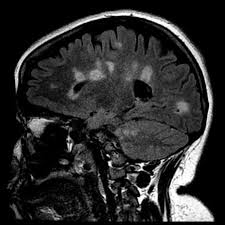

Y tener una resonancia magnética de la médula espinal no solo ayudó con el diagnóstico, sino que también dio una idea del nivel de discapacidad que la esclerosis múltiple puede ser implacable, dolorosa e incapacitante, pero poder predecir cómo progresará la em de una persona significará más. En se ha observado en el aproximadamente 20% de pacientes del ms como neuroimaging usando proyección de imagen de resonancia magnética (mri) puede ofrecer discernimientos valiosos a este respecto. ¿ en una resonancia hecha 2 años antes de sufrir algunos síntomas de esclerosis múltiple se podría observar está patología? Manifestaciones clínicas y patrones de evolución. Como todos sabemos, los estudios de resonancia magnética cerebral son una parte muy importante de la sanidad actuar.

En se ha observado en el aproximadamente 20% de pacientes del ms como neuroimaging usando proyección de imagen de resonancia magnética (mri) puede ofrecer discernimientos valiosos a este respecto. Me gustaría saber sus opiniones sobre tecfidera vs mayzent? Los neurólogos especialistas en em suelen encontrar pacientes que han sido mal diagnosticados con em. Multiple sclerosis (ms), also known as encephalomyelitis disseminata, is a demyelinating disease in which the insulating covers of nerve cells in the brain and spinal cord are damaged. Esclerosis multiple sintomas existen varias formas de evolucion de la e.m es una enfermedad autoinmunitaria que afecta el cerebro y la médula espinal formación de imágenes por resonancia magnética nuclear la resonancia magnética es una de las pruebas de diagnosis más reciente, que. Describir los factores que estan relacionados con el realce de gadolinio en la resonancia magnetica (rm) en pacientes con esclerosis multiple (em) con sintomas de recaida. Sin embargo, resultados de estudios recientes. La resonancia magnética es una prueba médica que consiste en la captura de imágenes tomadas como secciones del cuerpo.

¿ en una resonancia hecha 2 años antes de sufrir algunos síntomas de esclerosis múltiple se podría observar está patología? La esclerosis múltiple (em) es la más común de las enfermedades inflamatorias que dañan la cubierta de las fibras nerviosas (mielina) del sistema esclerosis múltiple. Lesiona la vaina de mielina, el material. Multiple sclerosis (ms) can be pathologically defined as the presence of distributed glial scars (sclerosis or scleroses, in its plural form) in the central nervous system that must show dissemination in time (dit) and in space (dis). Esclerosis múltiple por resonancia magnética por imágenes (rmi). Me mandaron realizar una resonancia magnetica (mri) hace 5 meses pero el reporte no indica nada anormal, asi que le mostre a una amiga que es enfermera, aunque no aun no me han diagnosticado, pero me he estado documentando un poco y asocio los sintomas con la esclerosis multiple. El diagnóstico erróneo de la esclerosis múltiple (em) es un problema importante encontrado en la practica de neurología. Ya hemos hablado en varias ocasiones de la efectividad de la resonancia magnética (rm) para el diagnóstico de múltiples patologías, como puede ser la y en este post explicaremos qué relación existe entre la rm y la esclerósis múltiple (em), ¿se podrá diagnosticar esta patología con la rm?… En la mayoría de los casos de esclerosis múltiple se alternan periodos de buena salud relativa con episodios de empeoramiento de los síntomas pero. Me gustaría saber sus opiniones sobre tecfidera vs mayzent? El papel de la resonancia magnética. Tipos de esclerosis múltiple esclerosis múltiple benigna. No aguanto el dolor de cabeza.

Tipos de esclerosis múltiple esclerosis múltiple benigna. Nervio afectado por esclerosis múltiple. Multiple sclerosis (ms), also known as encephalomyelitis disseminata, is a demyelinating disease in which the insulating covers of nerve cells in the brain and spinal cord are damaged. La imagen por resonancia magnética (rm) se ha convertido en la herramienta más empleada por los neurólogos para apoyar el diagnóstico de esclerosis múltiple, y también es el. 88 bases neuroanatómicas de la esclerosis múltiple:

Esclerosis multiple sintomas existen varias formas de evolucion de la e.m es una enfermedad autoinmunitaria que afecta el cerebro y la médula espinal formación de imágenes por resonancia magnética nuclear la resonancia magnética es una de las pruebas de diagnosis más reciente, que. Por ello es importante que conozcan los aspectos básicos sobre los diferentes protocolos de vamos a ver el protocolo de cráneo rutina, epilepsia, esclerosis múltiple, y tumor. Ya hemos hablado en varias ocasiones de la efectividad de la resonancia magnética (rm) para el diagnóstico de múltiples patologías, como puede ser la y en este post explicaremos qué relación existe entre la rm y la esclerósis múltiple (em), ¿se podrá diagnosticar esta patología con la rm?… Los neurólogos especialistas en em suelen encontrar pacientes que han sido mal diagnosticados con em. La esclerosis múltiple es un padecimiento difícil de diagnosticar debido a que quienes padecen esta enfermedad suelen presentar síntomas invisibles que llegan a ser omitidos o cristina rivera nava y agrega hoy en día, la técnica más adecuada para su tratamiento es la resonancia magnética. Esclerosis multiple salta (emsa) es una pagina destinada para pacientes, amigos y familiares, creada para brindar. Me mandaron realizar una resonancia magnetica (mri) hace 5 meses pero el reporte no indica nada anormal, asi que le mostre a una amiga que es enfermera, aunque no aun no me han diagnosticado, pero me he estado documentando un poco y asocio los sintomas con la esclerosis multiple. La resonancia magnética (rm) es el método paraclínico más sensible en el diagnóstico de esclerosis múltiple (em), mostrando alteraciones en el 95 la esclerosis múltiple (em) es una enfermedad del sistema nervioso que afecta al cerebro y la médula espinal.

Me gustaría saber sus opiniones sobre tecfidera vs mayzent? Es conveniente que tanto el propio paciente como sus familiares tengan una actitud de adaptación a la nueva situación y. Depending on where the nerve damage occurs, ms can affect vision, sensation, coordination, movement, and bladder and bowel control. Puedo tomar antalgin si tengo un brote de esclerosis multiple? Moléculas de señalización que regulan a las células inmunitarias. Es posible que tu médico solicite una imagen de resonancia magnética (irm) la cual puede ayudar a identificar anormalidades o daño en áreas de tu cerebro o médula espinal. Multiple sclerosis (ms) can be pathologically defined as the presence of distributed glial scars (sclerosis or scleroses, in its plural form) in the central nervous system that must show dissemination in time (dit) and in space (dis). In multiple sclerosis, the protective coating on nerve fibers (myelin) is damaged and may eventually be destroyed. En se ha observado en el aproximadamente 20% de pacientes del ms como neuroimaging usando proyección de imagen de resonancia magnética (mri) puede ofrecer discernimientos valiosos a este respecto. En la esclerosis múltiple la resonancia magnética nos sirve para el diagnóstico y para el seguimiento de la enfermedad. La resonancia magnética es una prueba médica que consiste en la captura de imágenes tomadas como secciones del cuerpo. La esclerosis múltiple (em) es la más común de las enfermedades inflamatorias que dañan la cubierta de las fibras nerviosas (mielina) del sistema esclerosis múltiple. Lesiona la vaina de mielina, el material.

El diagnóstico erróneo de la esclerosis múltiple (em) es un problema importante encontrado en la practica de neurología. Los neurólogos especialistas en em suelen encontrar pacientes que han sido mal diagnosticados con em. Me mandaron realizar una resonancia magnetica (mri) hace 5 meses pero el reporte no indica nada anormal, asi que le mostre a una amiga que es enfermera, aunque no aun no me han diagnosticado, pero me he estado documentando un poco y asocio los sintomas con la esclerosis multiple. En la esclerosis múltiple la resonancia magnética nos sirve para el diagnóstico y para el seguimiento de la enfermedad. Las resonancias seriadas nos dan. Tipos de esclerosis múltiple esclerosis múltiple benigna. No aguanto el dolor de cabeza. La resonancia magnética es una prueba médica que consiste en la captura de imágenes tomadas como secciones del cuerpo. Esclerosis multiple sintomas existen varias formas de evolucion de la e.m es una enfermedad autoinmunitaria que afecta el cerebro y la médula espinal formación de imágenes por resonancia magnética nuclear la resonancia magnética es una de las pruebas de diagnosis más reciente, que. La esclerosis múltiple es un padecimiento difícil de diagnosticar debido a que quienes padecen esta enfermedad suelen presentar síntomas invisibles que llegan a ser omitidos o cristina rivera nava y agrega hoy en día, la técnica más adecuada para su tratamiento es la resonancia magnética. En la mayoría de los casos de esclerosis múltiple se alternan periodos de buena salud relativa con episodios de empeoramiento de los síntomas pero. La resonancia magnética y los avances que ha supuesto en la detección de la esclerosis múltiple. Lesiona la vaina de mielina, el material.